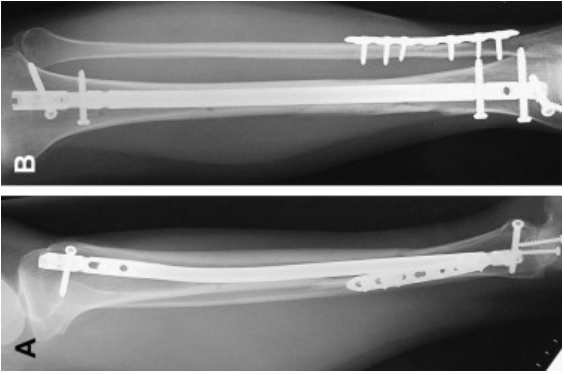

Femoral Fractures

The femur is arguably the most important bone in your body, ensuring effortless movement and mobility. But what happens when it becomes damaged? Find out how to identity the serious pains of a femur fracture and how to treat it.